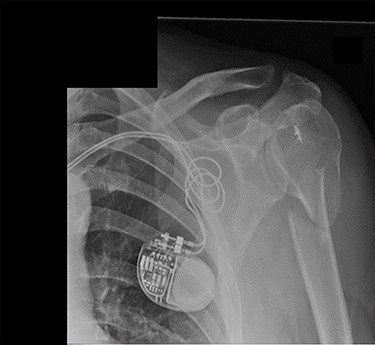

An X-ray of the left shoulder was performed, which revealed acceptable positioning of the fracture. Following a discussion with the patient, a mutual decision was made to manage the injury non-operatively and he was discharged with a collar and cuff sling. Subsequent clinical and radiological review at 1 week and 2 weeks post-injury showed the soft tissues to be healing well and the fracture to be well-positioned (Figs 5 and 6).

Antero-posterior view X-ray taken 2 weeks post-injury showing acceptable positioning of the fracture.